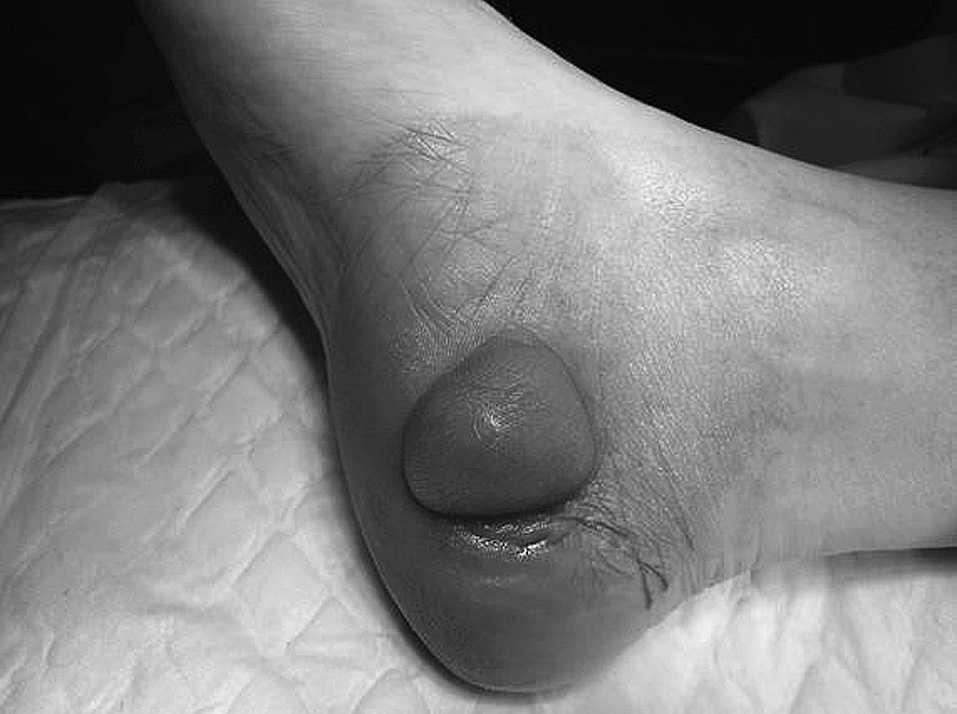

En el último mes apareció dolor en la zona de la tumoración, en forma de calambre con irradiación hacia la rodilla, sin ocasionarle limitación en su vida diaria. A la exploración se trataba de una tumoración dura, no de carácter pétreo, redondeada, no adherida a planos profundos, que adquiría un color violáceo, fácilmente accesible por cirugía ambulatoria (fig. 1).

Fig.1.Imagen macroscópica de la masa en el pie derecho.